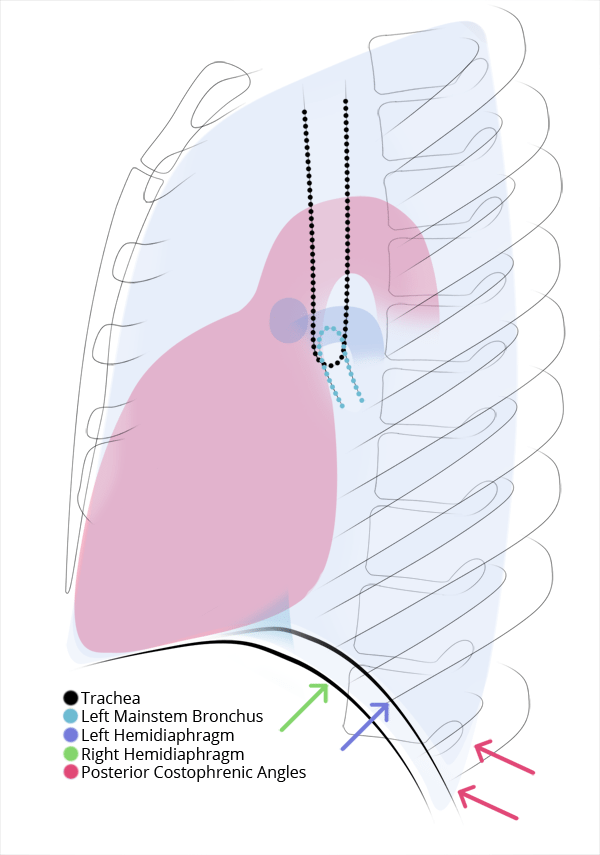

Chest

Chest

Chest radiograph & CT anatomy

Chest

Chest

Chest radiograph & CT anatomy